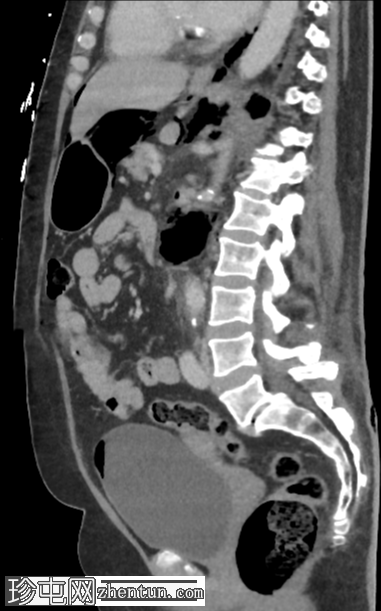

3.png

冠状位增强扫描(门静脉期)

左肾广泛破坏,伴有碎裂和气体膨胀

气体延伸至:

左侧输尿管;近端输尿管周围有气体包绕,并可见局灶性输尿管周围碎屑/积聚

进入膀胱

沿左肾静脉进入扁平的下腔静脉(脓毒性休克的特征)

沿十二指肠第二段(D2)进入肝门

进入肾周间隙,伴有坏死碎屑

经肾后间隙进入腰大肌、腹膜前脂肪和体壁

进入肠系膜后间隙、肾后间隙、侧圆锥间隙和联合筋膜间隙,直至股鞘

环绕左侧肾上腺、胃和脾脏,并位于膈下

经食管裂孔和主动脉裂孔进入纵隔

腹腔内气体

不对称性皮下炎症